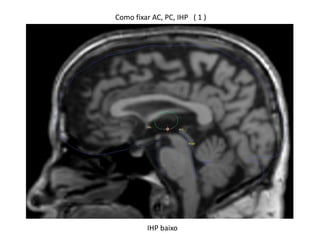

Como fixar AC, PC, IHP ( 1 )

IHP baixo